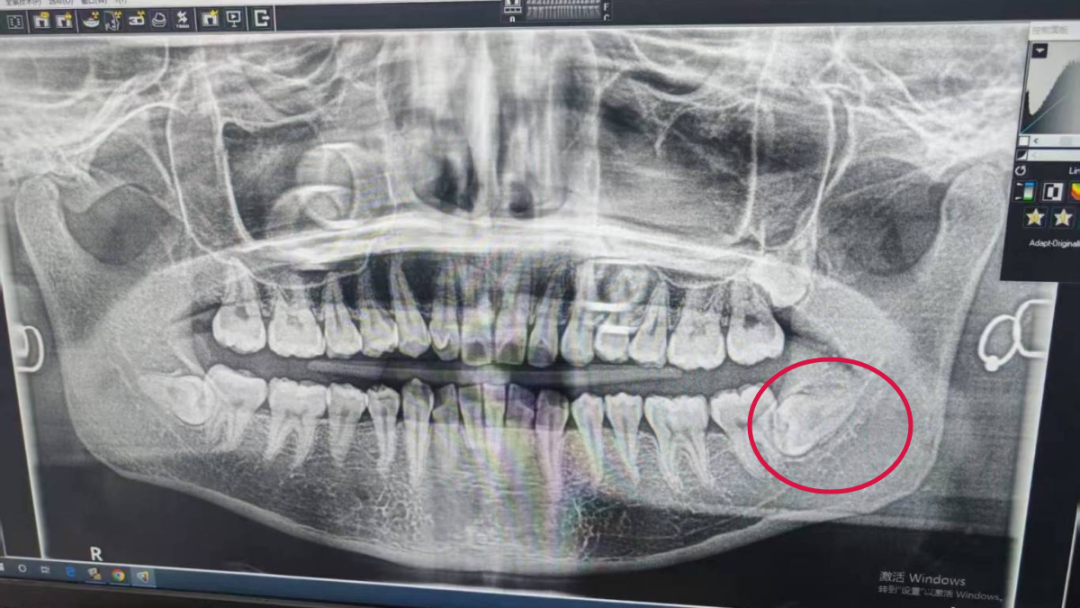

患者易小姐,女,左下完全埋伏阻生牙,牙根距离下颌神经管近,牙冠有骨质包裹,在局部浸润麻醉下,超声骨刀去除冠部骨质,增隙,颊舌向截冠,挺出近中牙冠后,获得良好视野,牙根无阻力挺出。

患者术前拍片